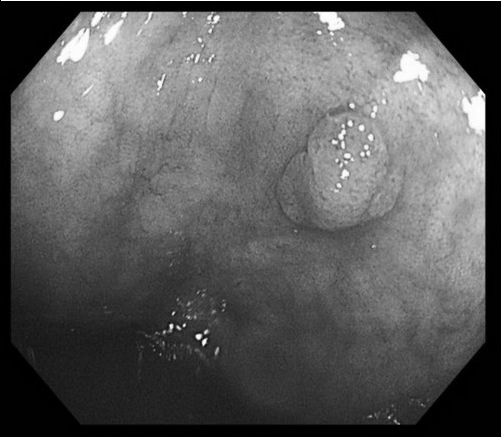

洪睿勝醫師發現腸內有盲腸管狀腺瘤息肉,隨即切除。(洪睿勝醫師提供)